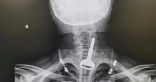

صحة القنفذة: فريق طبي يجري عملية تشخصيصة وتركيب دعامتين في الشرايين التاجية لمريض خمسيني

كشفت الشؤون الصحية بالقنفذة عن إجراء فريق طبي عملية تشخيصية وتركيب دعامتين في الشرايين التاجية اليسرى لمريض مصاب بالسكري يبلغ من العمر 54 عامًا، وذلك في مستشفى جنوب القنفذة العام.